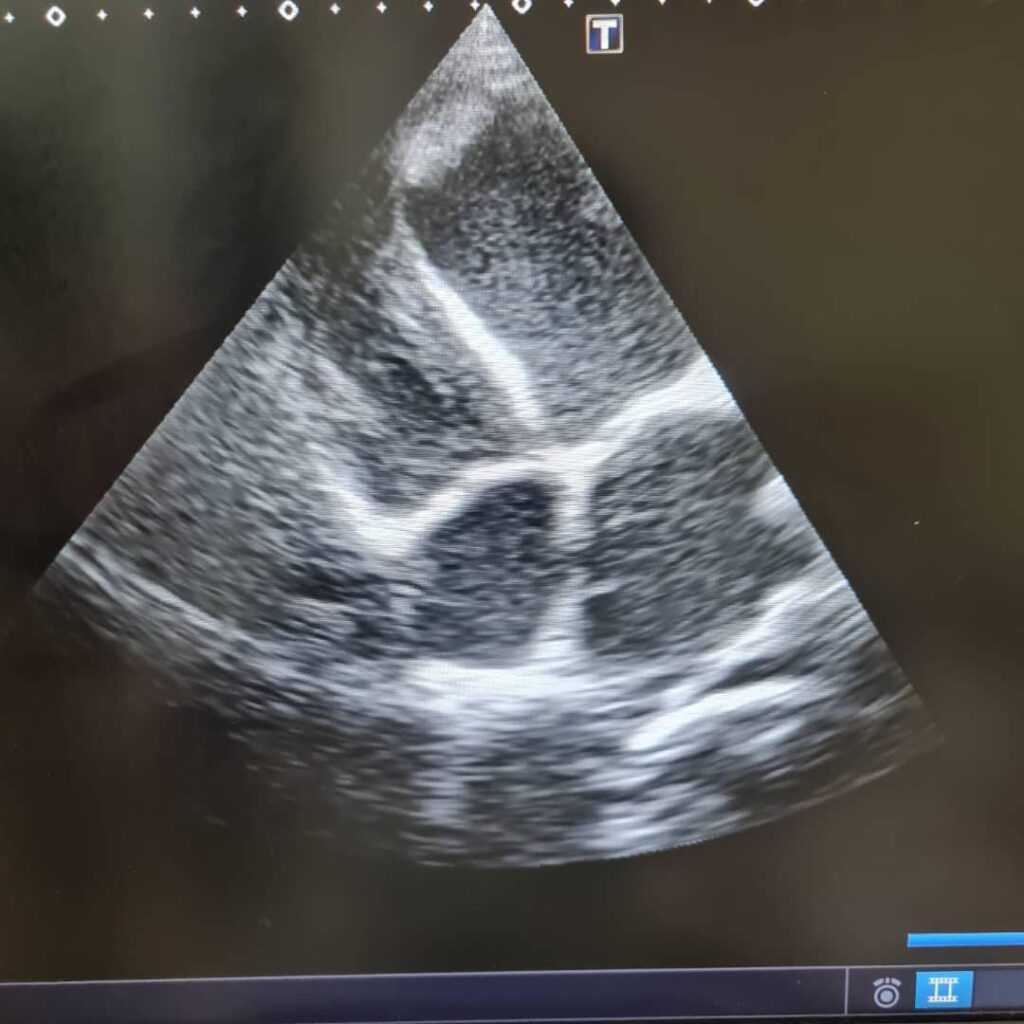

One was a 56-year-old woman, her life marked by repeated displacement. Each time she was forced to leave her home, she left behind not just her belongings but also consistent medical support. Her arthritis was already a significant burden, but a hidden danger was yet to be discovered. Just days after arriving at Al Naw, the dedicated doctors found a large blood clot in her heart, a silent killer that had gone undetected. Her chance of survival depended on swift intervention.

The second was an older man who had endured an eight-day journey on foot, each step a battle against the searing pain of a fractured hip – an injury sustained during a bombing incident. He arrived exhausted, hoping for the surgery that could save his limb. However, as the medical team examined him, another danger was revealed. Like the woman before him, he, too, had a lethal heart clot. His body, weakened by the journey, was running out of time and so was his heart.